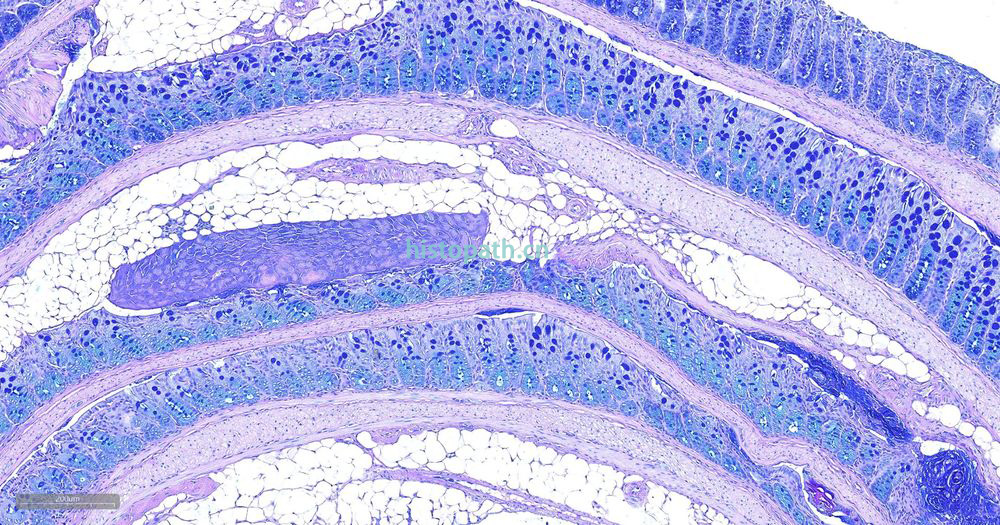

糖原染色是病理学中常规的染色方法之一,该法常用来显示糖原和其他多糖,该染色液不仅能够显示糖原,还能显示中性黏液性物质和某些酸性物质。

阿利新蓝和PAS技术联合使用可鉴别同一组织切片中的中性黏蛋白和酸性黏蛋白。这种技术也常用作广泛检测黏蛋白的手段。阿利新蓝可将唾液黏蛋白、硫黏蛋白和蛋白多糖染成蓝色。PAS技术可将中性黏蛋白染成深红/红紫色,同时将既含中性黏蛋白有含酸性黏蛋白的组织和细胞染成深浅不同的紫色,这是由于阿利新蓝与 Schiff试剂结合并反应。上述染色常可出现在含有中性黏蛋白和唾液黏蛋白的小肠杯状细胞中。

阿利新蓝是类铜钛花青染料,这种阳离子染料与酸性基团结合,也即阿利新蓝与组织内含有的阴离子基团如羧基和硫酸根形成不溶性复合物。分子中带正电荷的盐键与酸性黏蛋白多糖物质中带负电荷的酸性基团结合形成不溶性的复合物而呈蓝色,再与PAS进行复合染色,就能显示三种不同黏液物质成分。

染色结果: